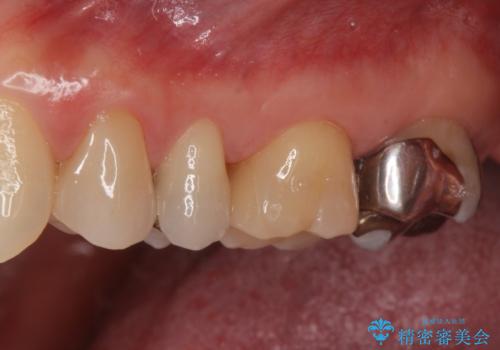

- 銀歯を無くしたいとの事で来院。

拡大鏡下でメタルを除去し虫歯がないことを確認してから白い詰め物、被せ物で治療を行いました。

適合の良い詰め物、被せ物が入りました。